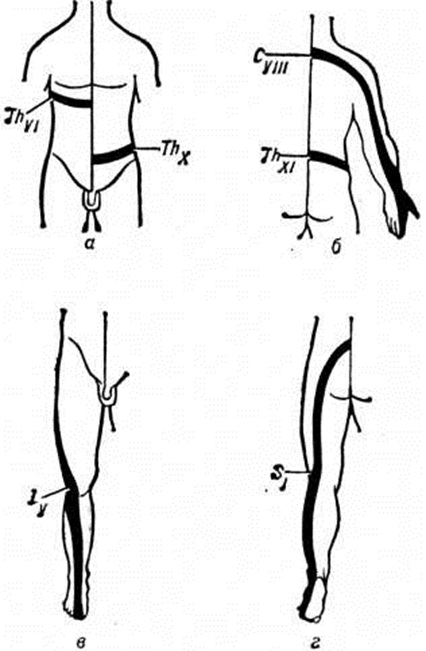

Расстройства чувствительности, по данным различных исследователей, встречаются в 67—90% случаев и отличаются большой вариабельностью распространения и степенью выраженности в ограниченных участках голени и стопы. Они проявляются вначале в виде парестезии (смотри полный свод знаний) либо нерезко выраженной гиперестезии, а затем гипестезии с участками гиперпатии (смотри полный свод знаний: Чувствительность, расстройства). Корешковый тип расстройств чувствительности является преобладающим (рисунок 1, в, г), а при нарушении спинального кровообращения они носят проводниковый и корешково-сегментарный характер.

Вначале появляются боли в шее с иррадиацией в зоны поражённых корешков, болям иногда предшествует онемение в этих зонах. Боли усиливаются при движении головой и шеей, распространяясь иногда на затылочную и грудную область. Иррадиация болей, по-видимому, связана с вовлечением в процесс Шейных узлов симпатического ствола, заднего шейного симпатического нерва. Характерны болевые точки в области шеи (вертебральные и паравертебральные), ограничение подвижности головы (преимущественно назад и в больную сторону), при нагрузке по оси позвоночника появляется болезненность в области шеи; иногда наблюдается кривошея (смотри полный свод знаний). Расстройства чувствительности, как правило, бывают корешкового типа (рисунок 1, а, б), вначале в виде гиперестезии, а затем гипестезии.